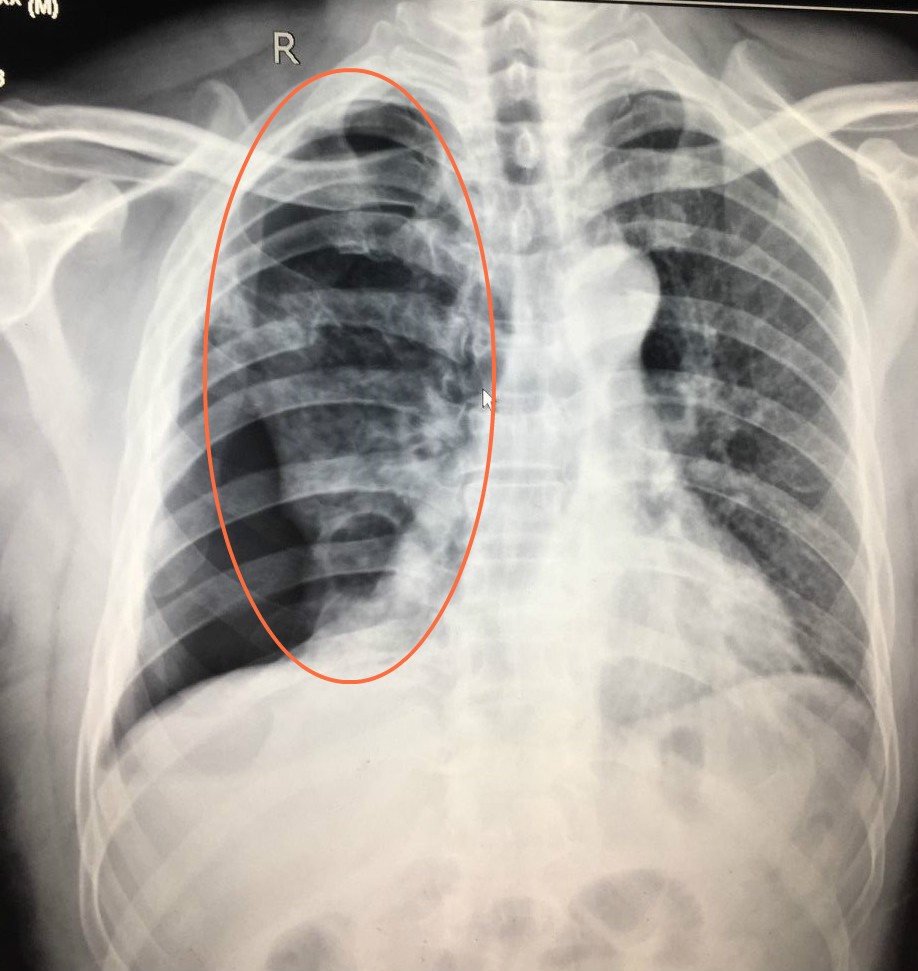

检查发现,李某右侧多根多处肋骨骨折伴肺挫裂伤和气胸,万幸的是,工友进行胸外心脏按压时并没有导致断裂的肋骨刺破肺部,才没有酿成大祸!如果肺部出血没有得到及时的救治,是十分致命的。